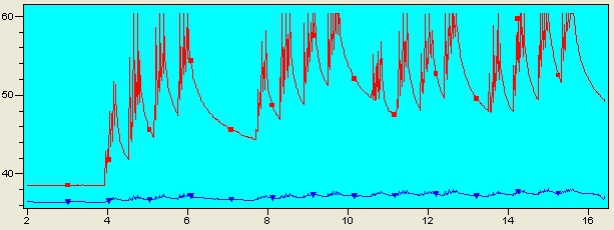

インティマレーザーの設定温度

インティマレーザーは温度調整の幅がとても広く、その方の膣の状態により照射する温度が異なってきます。

弱すぎれば効果が感じられない場合もありますが、強すぎると膣内が硬くなってしまうリスクもあります。

オートマティックで照射するマシンも出ていますが、当院ではあえてマニュアル照射を採用し、状態に応じてお一人ずつ温度設定を変えています。

インティマレーザーのショット数

インティマレーザーは蓄熱式のレーザーです。同じ場所で照射を繰り返すことで深くまで熱が入っていきます。

膣内粘膜の状態に応じてショット数をコントロールし、1度の照射で最大限の効果を引き出します。

インティマレーザーの照射時間

インティマレーザーを照射することで膣内の温度は上昇していきます。

当院では照射するごとに膣内の温度と血流を確認しながら最適な状態を目指します。

レーザーの施術は術者により大きく効果が異なります。